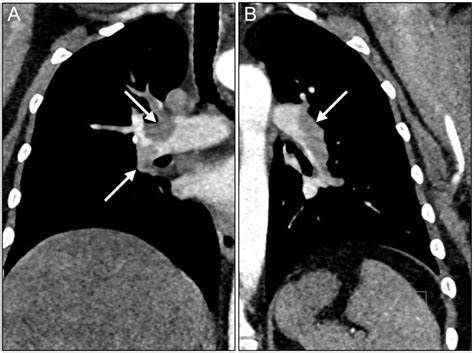

• Echocardiogram to assess cardiac function

• Laboratory tests to detect fetal cells or debris in the maternal bloodstream